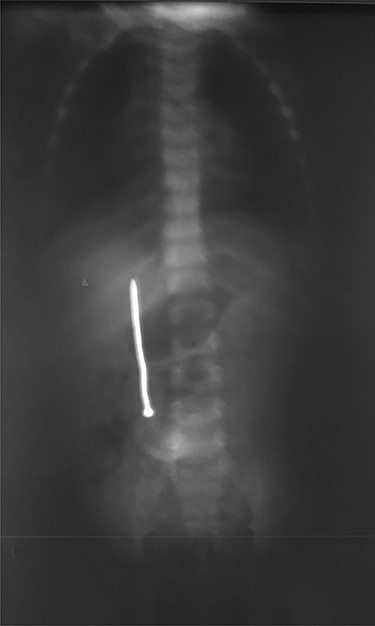

A 3-year-old male child was admitted in surgery department, with history of accidental ingestion of construction nail for 30 days, without any symptoms. Parents consulted in a peripheral hospital and plain abdominal radiography showed a nail projected in right-edge upon the lumbar spine (Fig. 1). Clinical observation was advised. The nail did not pass spontaneously and the child remained asymptomatic. Parents decided to consult again, but in our institution (surgery department). The child did not experience fever nor digestive symptoms (nausea, vomiting, abdominal pain, blood or color changes in stool). He had no prior history of FB ingestion.

Abdominal examination was normal. A repeat abdominal radiography was done. The nail’s position had not changed from the first X-ray site, with no free peritoneal air (Fig. 2).

Plain radiography plays the main role both in the diagnosis and the choice of operative interventional moment—either by pinpointing the radio-opaque image, or by showing certain FB characteristics, or by noting images suggesting complications (absent in our case), or even by projecting the FB in the same place over a period of time, an aspect inductive of fistula. In our case, right-edge superposition of the FB image upon the lumbar spine is characteristic of FB positioning in the second part of duodenum [5, 6]. Its persistence in the same place (the second part of the duodenum as in our case) suggests the presence of a duodenal fistula or perforation, which requires surgical intervention [7].